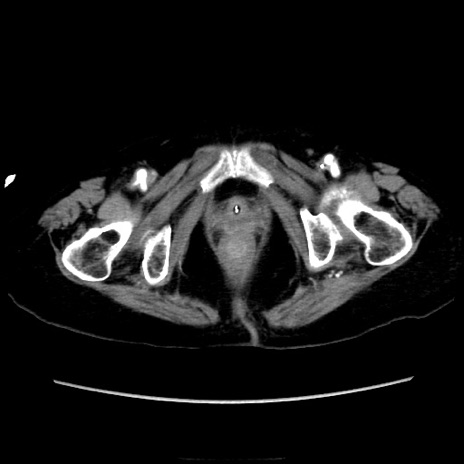

症例40(横断像)

【症例】90歳代女性

【主訴】腹痛・嘔吐

【現病歴】 食欲低下、嘔吐があり昨日他院受診。肺炎と診断され入院となる。入院後より腹部全体に圧痛あり。胃管留置され経過みていたが、症状持続するため、

当院転院となる。

【既往歴】胸椎圧迫骨折、胆石症

【身体所見】腹部:中央に激痛あり、圧痛あり、反跳痛不明

【データ】WBC 17100、CRP 18.82

横断像